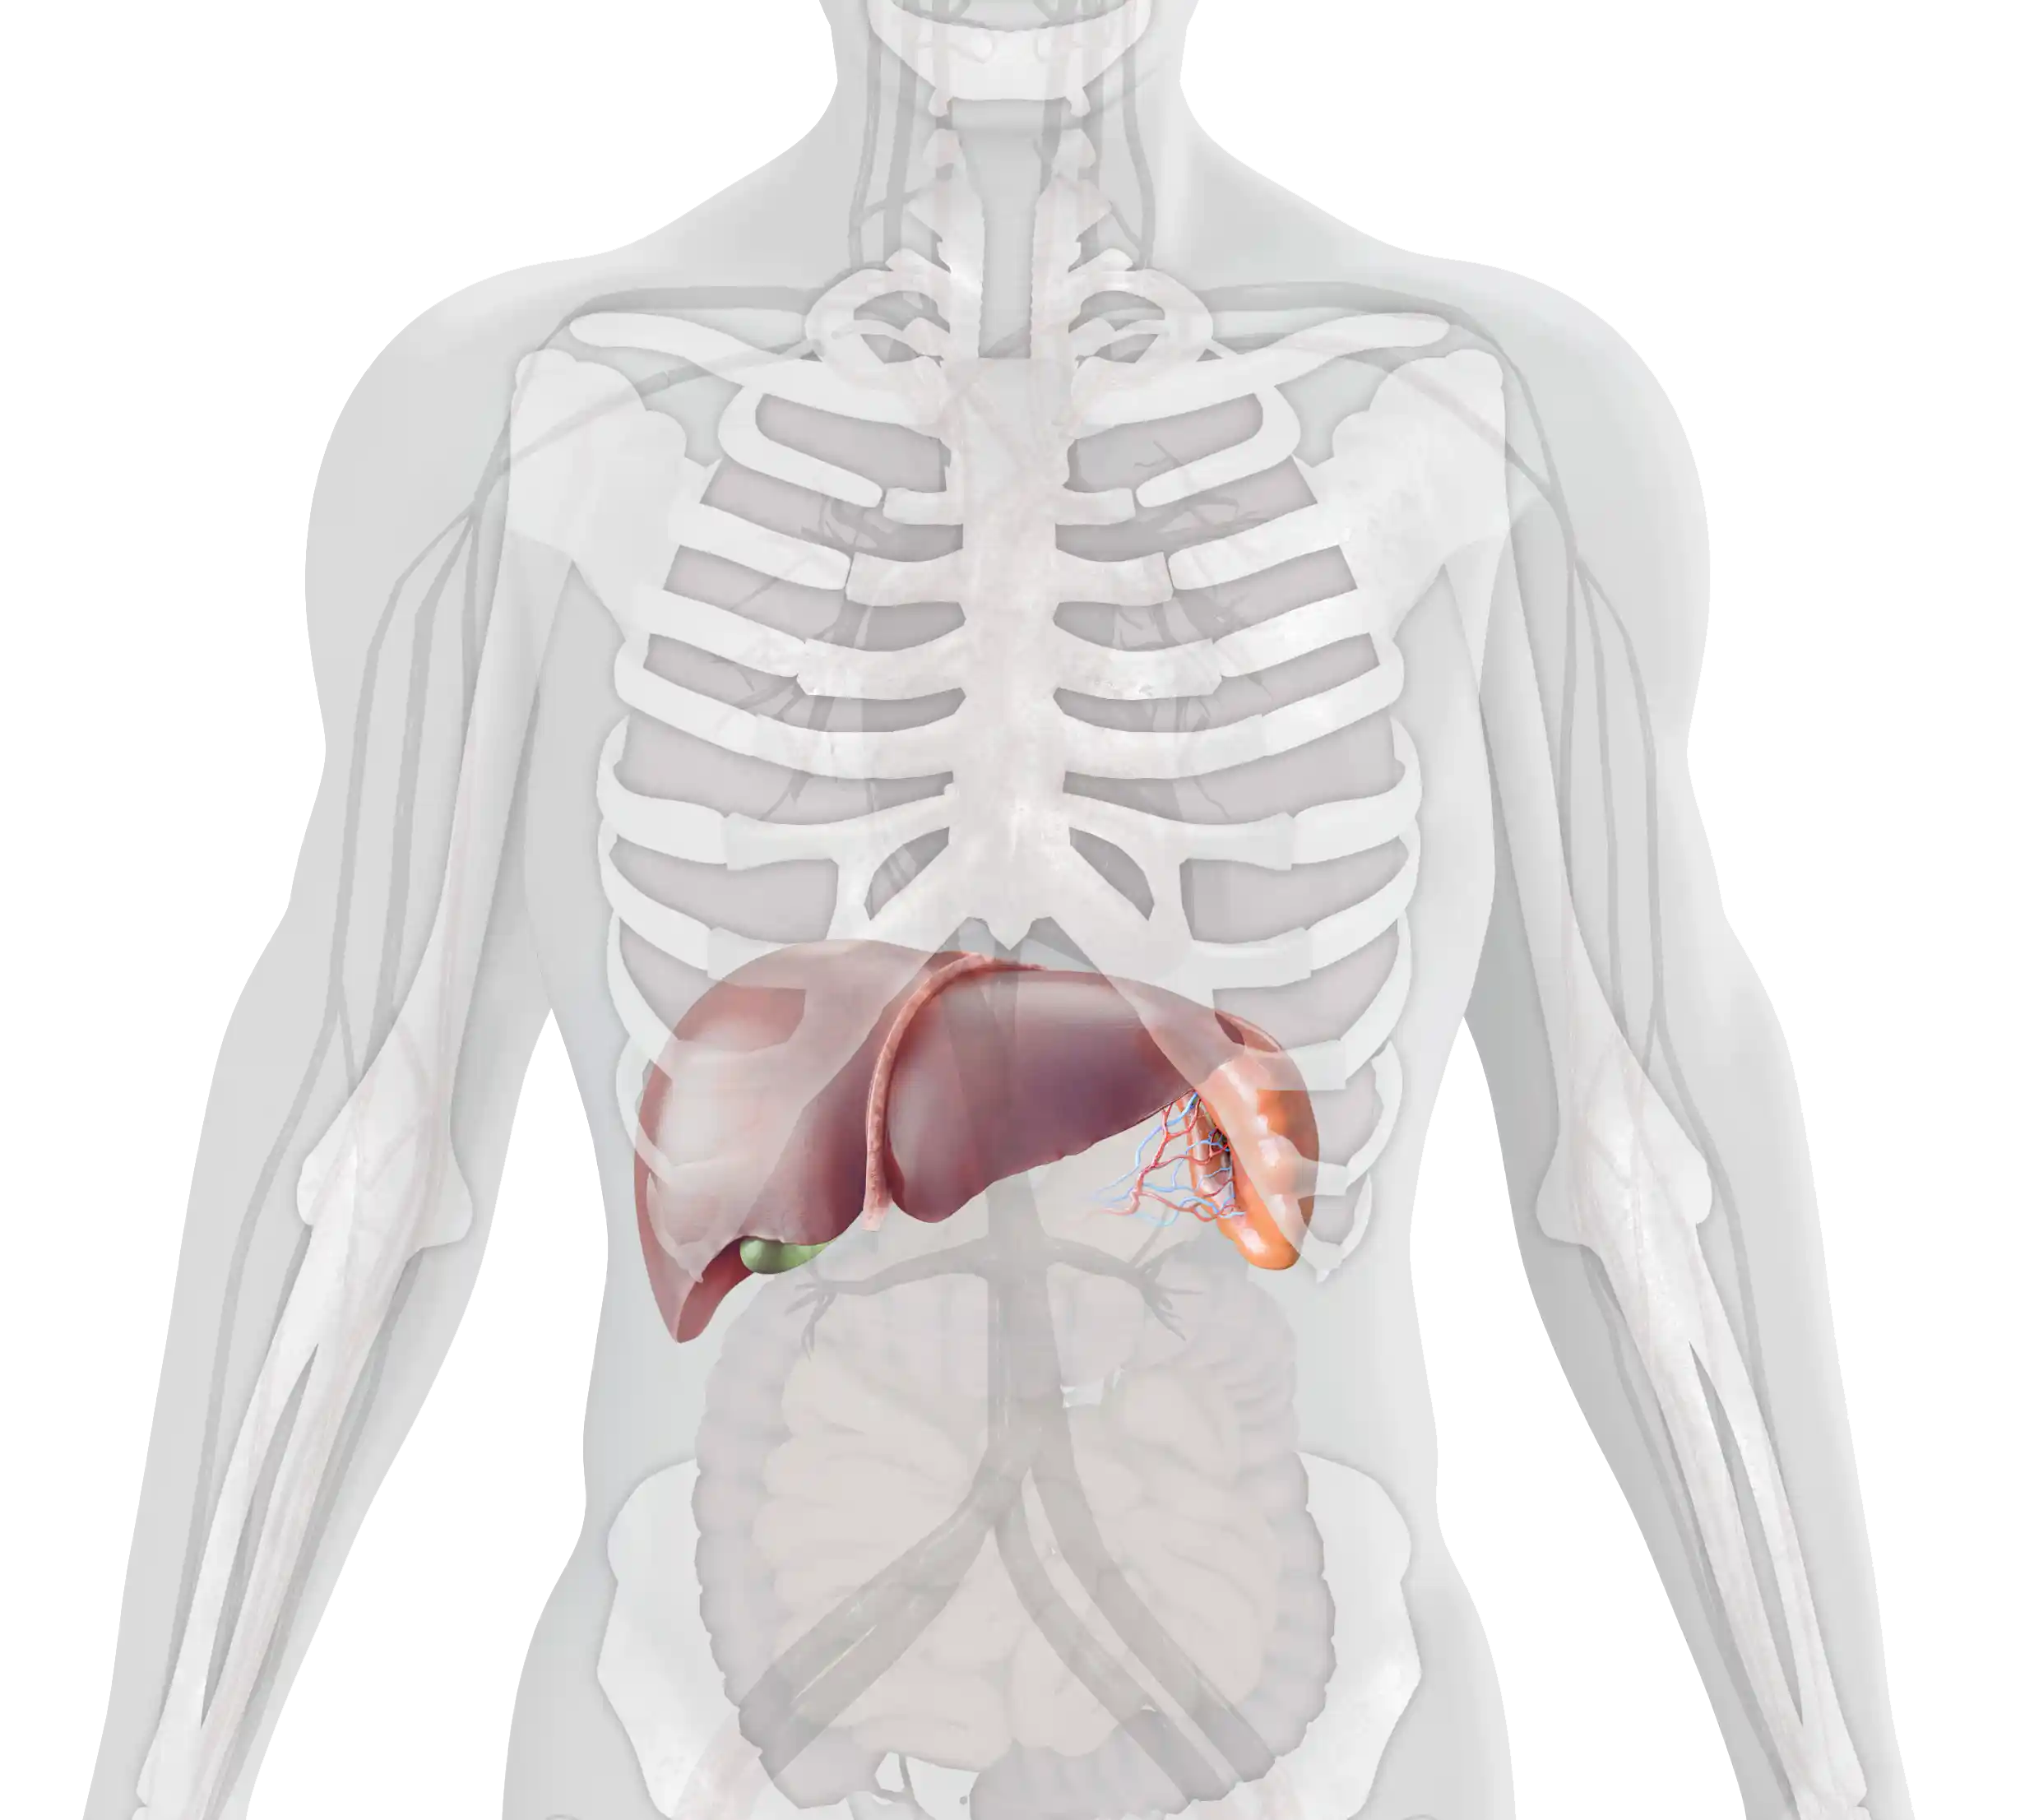

Gaucher disease (GD) is a rare, autosomal recessive lysosomal storage disorder, in which deficiency of the enzyme glucocerebrosidase leads to the accumulation of its substrate glucocerebroside throughout the body, primarily in the spleen, liver, and bone marrow.1–3 The accumulation of glucocerebroside in the different areas of the body leads to the progressive, multi-systemic, and heterogeneous nature of the disease.1,4

- Gaucher cells infiltrate organs and tissues enriched in cells of the mononuclear phagocyte system, e.g., the spleen, liver, and bone marrow.1,9,10

- Over time, they displace normal cells resulting in progressive impairment; the liver and spleen may become enlarged, which can interfere with normal functioning and cause a painful and swollen abdomen.1,8,9,11

Splenomegaly occurs in 95% of patients with GD1. It may be one of the first and most physically prominent presentations of GD1 in patients. Splenomegaly results in abdominal distension and early satiety.4–7 Many patients complain of acute abdominal pain, which can be worsened by splenic infarction.1,8

Enlargement of the liver occurs in 80% of patients with GD1, also contributing to abdominal pain and early satiety.1,5,7 Hepatomegaly may progress to liver disease and cirrhosis.1,4